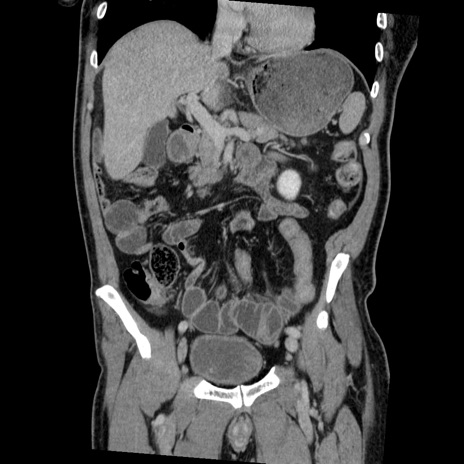

症例22(冠状断像)

【症例】50歳代男性

【主訴】腹痛

【現病歴】AVMからの被殻出血のため回復期リハ病棟入院中。 本日午後3時頃急に下腹部痛が出現した。

【既往歴】AVM、被殻出血、虫垂炎、高血圧

【身体所見】意識晴明、左半身不全麻痺、会話の理解は良好、36.5°C、腹部:膨隆、全体に板状硬、下腹部正中に圧痛点あり、反跳痛-、筋性防御不明、右下腹部にope scar

【データ】WBC 9400、CRP 0.06